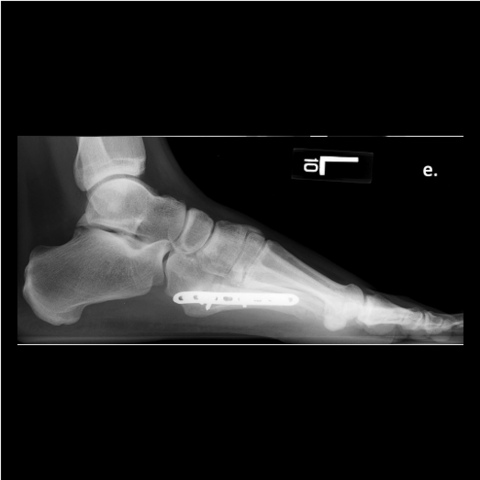

Figure 6d

Figure 6d. Plating of the fracture since screw fixation was not possible, and the patient refused external fixation for a second time.